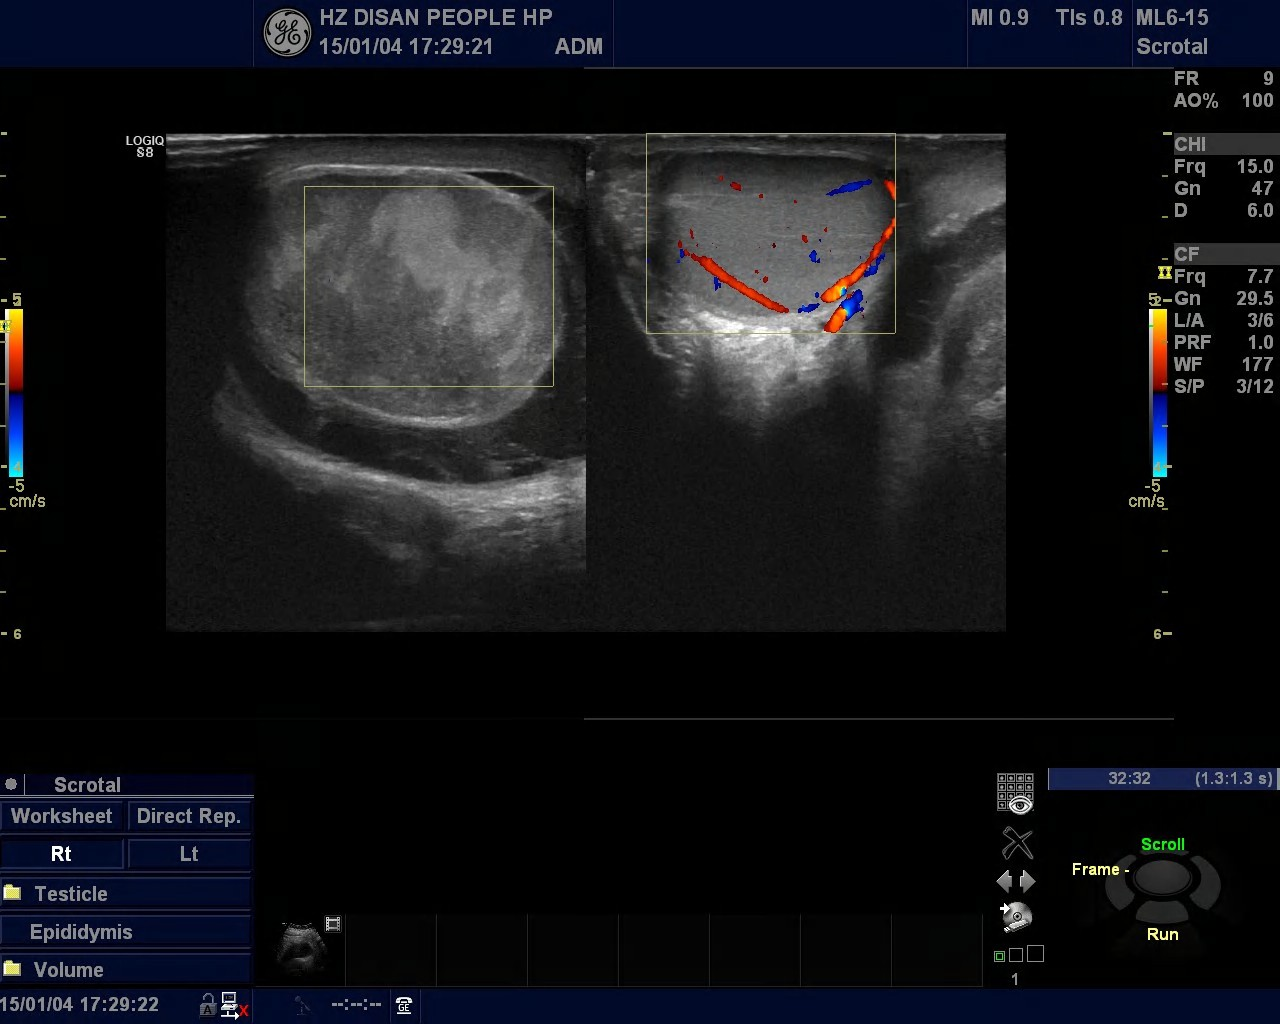

我院超聲科近期發(fā)現(xiàn)多例睪丸扭轉(zhuǎn)的病人。有一天下午超聲科來了一位下腹疼痛的男病人,醫(yī)生開了一張睪丸、附睪的彩超檢查單,后來檢查發(fā)現(xiàn)病人左側(cè)睪丸稍大、血流信號較右側(cè)減少,未排除睪丸扭轉(zhuǎn)可能,建議進一步檢查。泌尿外科醫(yī)生看到檢查報告單,加上病人的臨床癥狀,考慮左側(cè)睪丸扭轉(zhuǎn)。醫(yī)生建議急診手術(shù),手術(shù)結(jié)果證明是睪丸扭轉(zhuǎn)。如果病人再晚一點就診或手術(shù)的話,病人的睪丸就會壞死,恐怕只能悲催地手術(shù)切除了。

睪丸扭轉(zhuǎn)(torsion of testis)又稱精索扭轉(zhuǎn),與陰囊先天性解剖發(fā)育異常密切相關(guān),包括精索過長,精索鞘膜附著異常形成“鐘擺式”睪丸以及睪丸引帶缺如等。深睡眠、劇烈運動、撞擊等狀態(tài),可使精索上的提睪肌強烈收縮,導(dǎo)致扭轉(zhuǎn)并引起睪丸的急性血液循環(huán)障礙,臨床并不罕見。

睪丸扭轉(zhuǎn)為泌尿外科常見急癥之一。睪丸扭轉(zhuǎn)會使睪丸的血液供應(yīng)減少,如果不及時發(fā)現(xiàn)并解除 ,就可導(dǎo)致睪丸壞死。一般來說 ,扭轉(zhuǎn)后 6小時內(nèi) ,可采用手術(shù)緩解扭轉(zhuǎn) ,既可保留睪丸不影響生育 ,又可預(yù)防復(fù)發(fā)。扭轉(zhuǎn)超過6小時,睪丸不容易救活,一旦壞死 ,不得不“忍痛割愛”,予以手術(shù)切除。

睪丸既是生殖器官,又是內(nèi)分泌器官,對于男性的重要性不言而喻。所以,我院泌尿科醫(yī)生建議,如果出現(xiàn)睪丸疼痛,沒有好轉(zhuǎn)反而越來越疼的話,要特別警惕有無睪丸扭轉(zhuǎn),趕緊去醫(yī)院就診。睪丸扭轉(zhuǎn)一旦確診,應(yīng)及時進行手術(shù),即使懷疑有扭轉(zhuǎn),也應(yīng)盡早手術(shù)探查。如果病人沒有及時就醫(yī)可能會造成無法挽回的嚴重后果。(超聲科 馬李明)